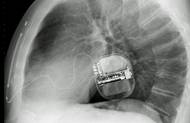

Profesor Petr Neužil, přednosta Kardiologické kliniky 1. LF UK a Fakultní nemocnice Motol a Homolka, doufá, že bude přibývat českých soukromých firem ochotných investovat do inovátorských postupů ve zdravotnictví. V rozhovoru pro Novinky popisuje, jak vznikl nový český katetr, který podle něj přináší revoluci v léčbě srdeční arytmie.